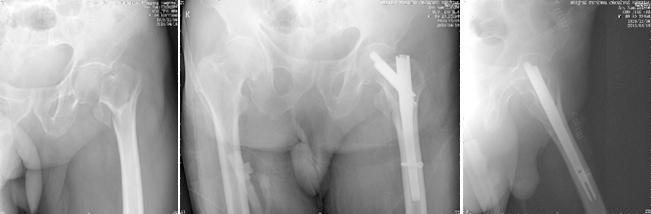

随着我国人口老龄化,骨质疏松骨折发病率连年上升,髋部骨折、脊柱压缩骨折、桡骨远端骨折、肱骨近端骨折四大骨质疏松骨折成了困扰老年人的常见病和多发病。一旦发生骨质疏松骨折,轻则致残,重则由于卧床并发症造成死亡,对于家庭和社会造成沉重负担。北京清华长庚医院创伤骨科中心应用髓内钉、椎体成形等微创技术,结合传统的钢板螺钉固定、关节置换等手术方案,为多名90岁以上超高龄老人进行了手术,获得术后第1天即可下地行走的良好效果,让更多骨折后的老人重返社会。

高龄老人髋部骨折髓内钉微创治疗,术后即可下地恢复活动。